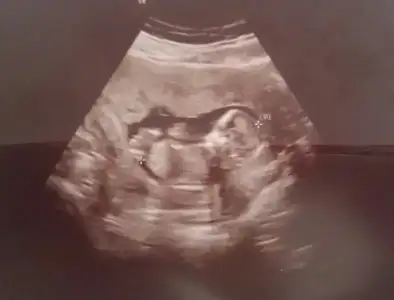

Bu nub bacak arası mı oluyor? Yukarı doğru kalkık olanlar bacak değil mi? Benim ufaklık içinde bir tahmin yapar mısınız? Eki Görüntüle 2091858 Eki Görüntüle 2091858

Ne kadar net çekilmiş bir üsg ilk defa bu kadar net görüyorum , tam bir erkek hem de bacaklarını açmış biri saga biri sola sağa taraf olan biraz belli olmuyor soldaki tam belli bir de kıvrık olan da kordon bağı :) maşallah canım Rabbim nazarlardan korusun sağ salim doğsun inşallah